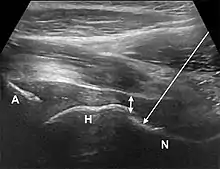

Anterior longitudinal approach. The needle is introduced from an inferior and anterior approach, lateral to the femoral neurovascular bundle (arrow). A, acetabulum; H, femoral head; N, femoral neck; double arrow – anterior joint recess.[1]

• The anterior longitudinal approach: the probe is aligned along the long axis of the femoral neck. The needle is introduced from an anteroinferior approach and is passed into the anterior joint recess at the femoral head-neck junction.